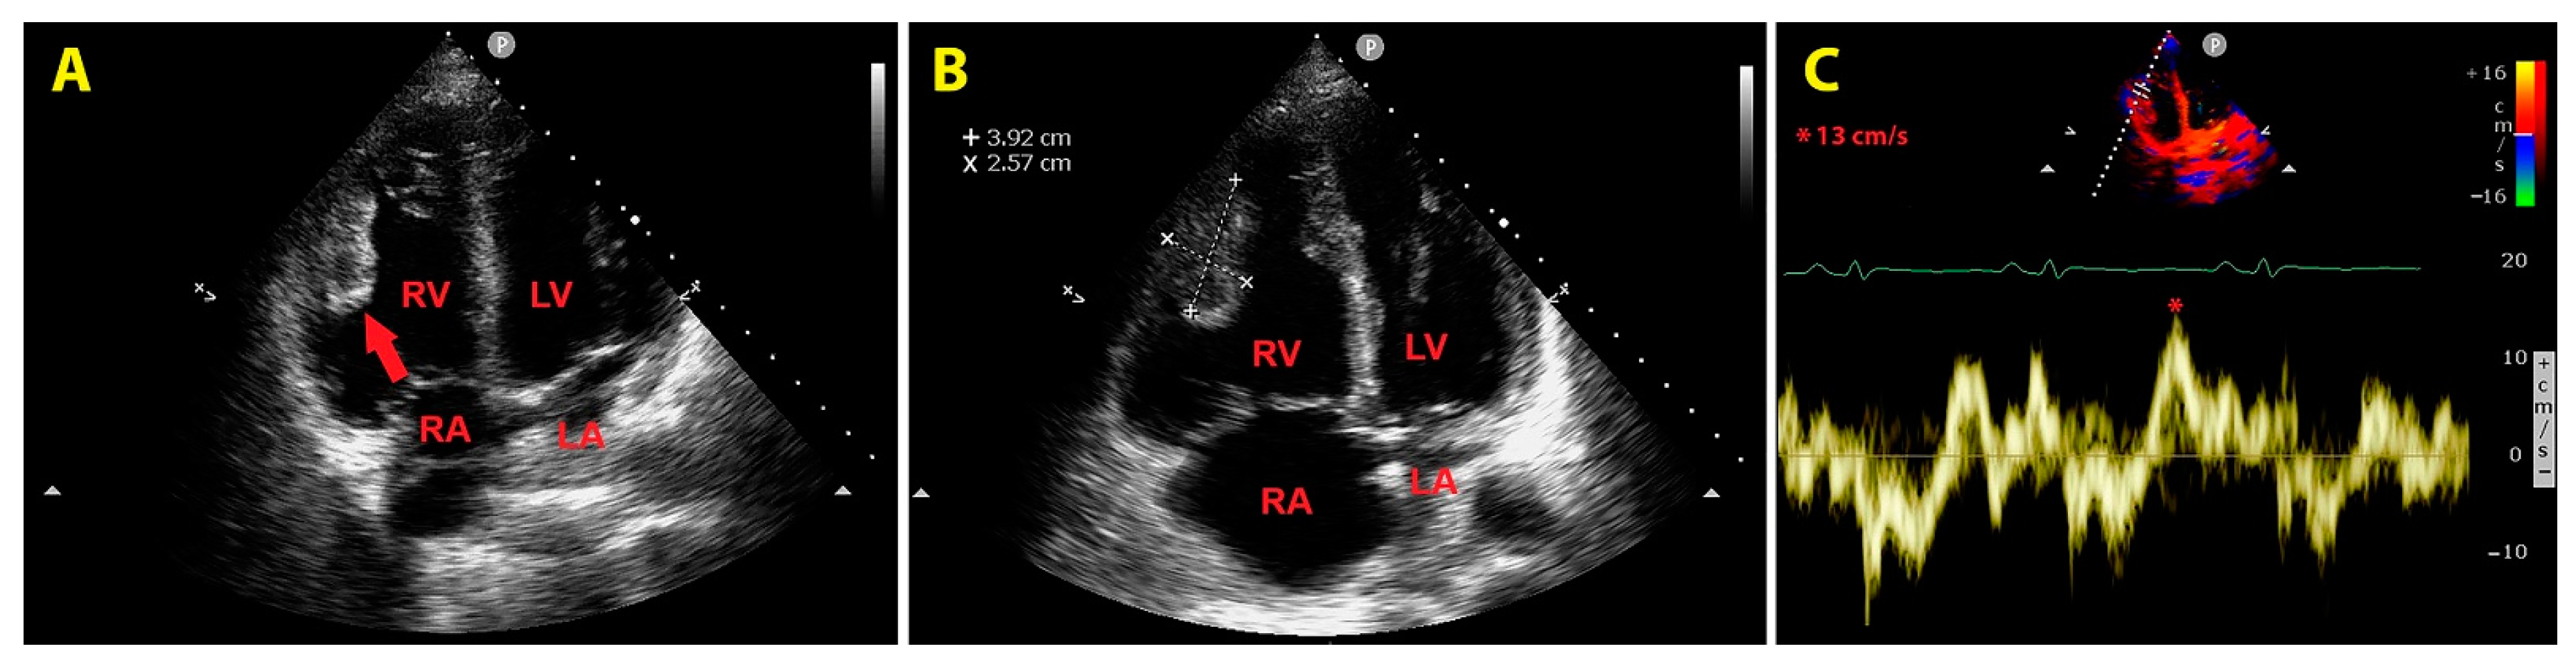

An urgent bedside echocardiogram highlighted a significant dilatation of right-sided cardiac chambers (RV to left ventricular basal diameter ratio = 2.4; RV inflow tract diameter = 60 mm), RV hypertrophy (RV free wall thickness = 10 mm) and mild hypokinesia of the RV lateral wall, as assessed by tricuspid annular plane systolic excursion (TAPSE) magnitude (17 mm); a moderate tricuspid regurgitation was present. The peak tricuspid regurgitation velocity (TRV) was 3.4 m/s, indicating high probability of pulmonary hypertension (PH); the inferior vena cava was significantly dilated (transverse diameter = 2.8 cm), with inspiratory excursions <50%; accordingly, the estimated systolic pulmonary artery pressure (sPAP) was 60 mmHg. On RV focused apical four-chamber view, a large sessile echogenic formation with hyperechoic edges (size 3.9 cm x 2.6 cm), attached to the mid-apical portion of the RV free wall, protruding into the RV cavity, was detected (Figure 3, A and B). By placing a 5 mm sample volume of pulsed wave (PW)-tissue Doppler imaging (TDI) at the level of the mobile portion of RV mass, a RV mass peak antegrade velocity (Va) of 13 cm/s was obtained; moreover, on PW-TDI, the RV mass showed a pattern of incoherent motion, totally discordant and independent from the surrounding myocardial tissue (Figure 3C).

Figure 3. Transthoracic echocardiography. Right ventricular focused apical four-chamber view. (A) Large sessile echogenic formation with hyperechoic edges (red arrow), attached to the mid-apical portion of the right ventricular free wall, protruding into the RV cavity. (B) Measurement of the right ventricular mass size. (C) Assessment of the right ventricular mass peak antegrade velocity by pulsed wave tissue Doppler imaging. The right ventricular mass showed a pattern of incoherent motion, totally discordant and independent from the surrounding myocardial tissue. LA, left atrium; LV, left ventricle; RA, right atrium; RV, right ventricle. The symbol * indicates the right ventricular mass peak antegrade velocity.